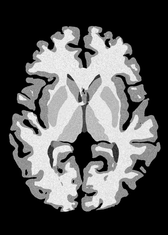

4.2 Registration to a 100 micron ex-vivo brain MRI volume

To showcase the efficacy of our method on real large scale images, we register a 250 in-vivo MRI image (Lüsebrink et al., 2017) to a 100 ex-vivo FLASH human brain volume (Edlow et al., 2019). This represents an inverse problem with more than 11.2B optimizable parameters (compared to 20M for clinical datasets), or 44.8GB of GPU memory. The entire problem does not fit on most GPUs, necessitating distributed multimodal registration. We optimize a composite transform - affine followed by a diffeomorphic mapping; details can be found in Section E.1. Multimodal deformable registration took 58 seconds on 8 NVIDIA A6000 GPUs, which is unprecedented at this resolution. Fig. 6 shows qualitative results, highlighting the ability to register highly detailed structures such as cerebellar white matter; these structures are not visible at macroscopic scales. The resultant advantages of performing registration at this scale can allow researchers to characterize the neuroanatomy at microscopic resolutions and allow morphometric analysis of cortical layers and subcortical nuclei among other structures.